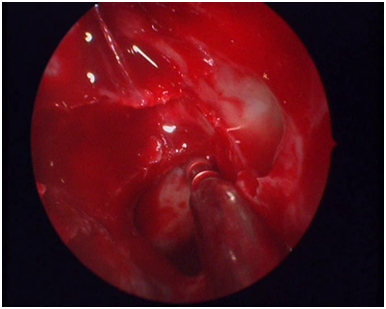

Using the same instruments, every ethmoid septum attached to the skull base and the lamina papyracea is gradually removed. This will serve a dual purpose: It will render the bed to receive the graft smooth and it will facilitate the removal of the mucosa. In order for the skin graft to survive, no remnant of nasal mucosa is left covering the lamina papyracea, the fovea ethmoidalis and the lateral surface of the middle and upper concha. The mucosa is meticulously removed making use of the round knife used in the ear surgery (Figure 4). The mucosa of the lateral surface of the middle and upper concha is removed making use of the microdebrider. The last action taken before the insertion of the graft is to suture-fix the middle concha to the septum with an absorbable stitch.

Figure 4 The use of the otosurgical round knife.

Figure 5 Picture of the surgical cavity ready to receive the graft.